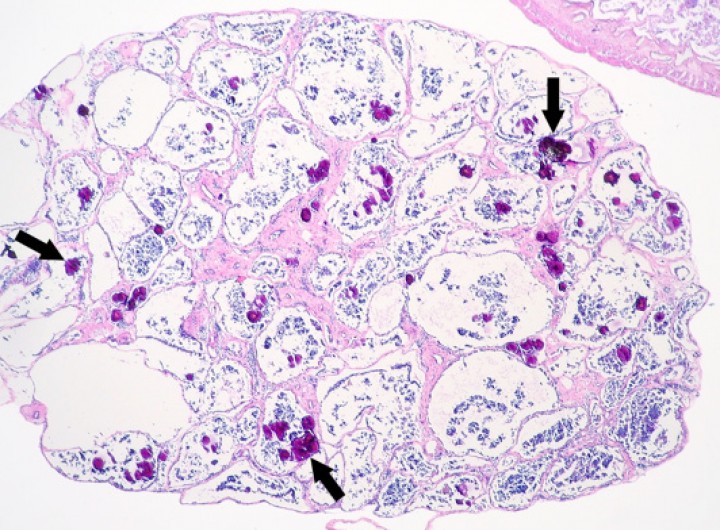

En 19 de los 131 anfibios (14,5%) se observó mineralización de tejidos blandos, que afectó generalmente al epitelio renal tubular, a los túbulos seminíferos del testículo (Fig. 1), a la piel y/o a los pulmones. Ocasionalmente, los depósitos de mineral en tejidos blandos estaban rodeados por células gigantes multinucleadas. Diecisiete de estos 19 anfibios padecían enfermedad renal, inflamación granulomatosa frecuentemente sistémica, cuadros catabólicos y/o procesos de enfermedad que pudieron causar deshidratación (como la enteritis por estrongiloidiasis) o mineralización por otros mecanismos (como producción de sustancias con actividad parathormona en el caso de linfoma). En 2 de los 19 anfibios, la mineralización correspondía a calcinosis circunscrita subcutánea asociada a cestodos enquistados (ver Fig. 10A del artículo “Enfermedades infecciosas y parasitarias en anfibios en cautividad: estudio retrospectivo de 131 pacientes”[ Juan-Sallés C, Almagro V, Carbonell L, Valls X, Montesinos A, Fernández Bellon H: Enfermedades infecciosas y parasitarias en anfibios en cautividad: estudio retrospectivo de 131 pacientes. Clín Vet Peq Anim 2020; 20(1):15-27. [Clin Vet Peq Anim] ]). Uno de los anfibios, una rana toro (Pyxicephalus adspersus) que murió por una gastroenteritis fibrinonecrotizante-enfisematosa y hemorrágica bacteriana aguda, fue remitido con historial de lesiones de depósito mineral alrededor de las vértebras (Fig. 2); sin embargo, este hallazgo correspondía a depósitos de calcio en los sacos endolinfáticos en anfibios, considerados normales por lo menos hasta un cierto grado no establecido de forma específica.[ Pessier AP. Amphibia. En: Terio KA, McAloose D, St. Leger J, ed. Pathology of wildlife and zoo animals. London: Academic Press; 2018; 915-944. ] La ausencia de mineralización metastática de tejidos blandos en esta rana sugiere que toleró este grado de almacenaje de calcio sin consecuencias clínicas obvias.

<p>Testículo; rana tomate (<em>Dyscophus guineti</em>). Numerosos túbulos seminíferos contienen depósitos de mineral (flechas). Hematoxilina-eosina, x44.</p>

Testículo; rana tomate (Dyscophus guineti). Numerosos túbulos seminíferos contienen depósitos de mineral (flechas). Hematoxilina-eosina, x44.